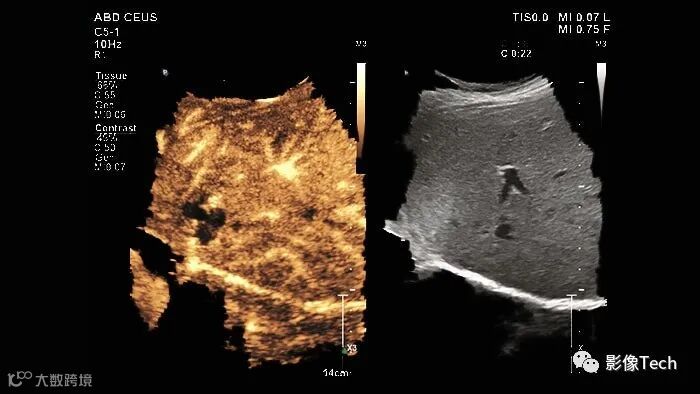

在诊断和治疗癌症患者时,进出可疑病变的血流动态可以为临床医生提供有价值的诊断信息。例如,通过肝脏肿瘤的血流可以深入了解癌症扩散的可能性。目前评估病变血流的护理标准需要静脉注射碘造影剂,但一些患者对此的耐受性不佳。在这种情况下,超声造影(CEUS)正迅速成为可行的替代方案,成为病变表征日益重要的工具。

CEUS 是一种超声成像技术,通过使用一种特殊的造影剂来增强图像的对比度和清晰度。在CEUS中,医生会向患者注射一种含有微小气泡的造影剂,这些微小气泡可以反射超声波并产生明亮的图像。这些气泡可以进入血液循环并集聚在特定的组织或器官中,从而提供更详细的血流信息和组织灌注情况。

CEUS在临床上被广泛应用于肝脏、肾脏、心脏、乳腺等器官的检查,可以帮助医生更准确地诊断和评估病变、肿瘤、血流动力学等情况。

此外,CEUS 不使用碘造影剂,而是利用基于患者呼吸排出的惰性气体的微泡造影剂。随着飞利浦超声系统 EPIQ Elite 引入了飞利浦微血管成像超分辨率超声造影(CEUS)应用,CEUS 成像现在的空间分辨率比之前的产品提高了 200%。

德国慕尼黑 LMU大学的放射学教授 Dirk-André Clevert 表示,飞利浦的微血管成像让医生能够可视化造影剂流入病变的模式,并显示它如何随时间变化,这增强了医生在评估不确定病变时的诊断信心。